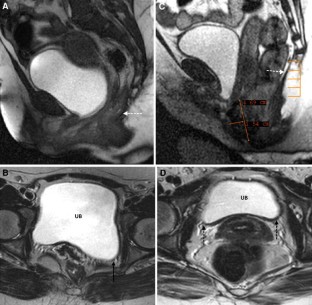

Fig. 1